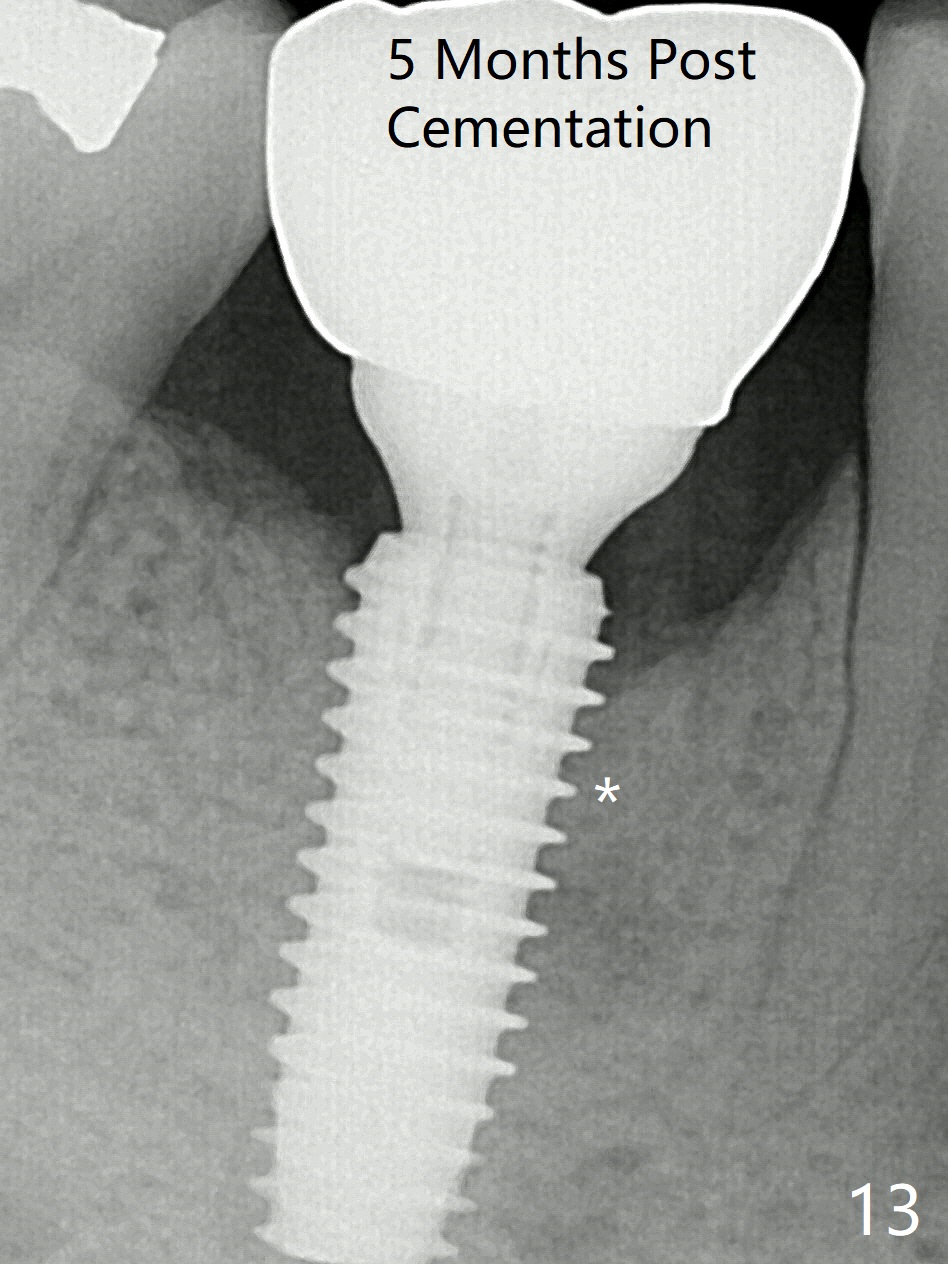

Preop oral Amoxicillin seems to be associated with reduction in the buccal and lingual (Fig.3 arrow) fistulae at #30, but there is mesiobuccal swelling (Fig.1 *) with 7 mm pocket (Fig.2). Osteotomy is initiated in the middle of the septum (Fig.3-5 S). As the osteotomy increases, it shifts mesially (Fig.6 arrow). Guided surgery is able to reduce shifting. A 5x13 mm implant is not seated completely (Fig.7) apparently due to osteotomy shifting. After removal of the bone from the osteotomy distally, the implant remains unseated with lower torque value (Fig.8). Following reuse of the 4.3 mm drill deeper by 1-2 mm, the implant is seated to a satisfactory depth (Fig.9 with increase in torque to 50 Ncm) with placement of Vera Graft (*) and a 7.5x4(3) mm abutment. After a second round of allograft placement (Fig.10 *), the implant is found to be 4 mm from the IAC. At the later stage of osteotomy, the coronal end of the septum is destroyed with loss of osteotomy depth landmark. It is apparent that the soft tissue landmark may be more reliable. The implant threads appear to be covered by the bone graft 3.5 months postop (Fig.11). The abutment is changed to 6.5x5(3) mm one before impression with minor margin prep. The bone density seems to increase 5 months postop, i.e., immediately post cementation (Fig.12) and 10 months postop (5 months post cementation (after retightening abutment), Fig.13 (*)). Periimplantitis develops mesiobuccally, consistent with bone loss 1 year 7 months post cementation (Fig.14 *); the implant seems to have been buccally placed. Bone graft is necessary with PRF or GEM21S if the vein is small and 6-month membrane with a hole around a 7.5x4(4) cemented abutment for easy wound closure. Take 5x5 CM CBCT to determine which wall has defect, buccal or lingual. Check mesial contact. If so, remove the crown, reseat the abutment (possible incomplete seating) and re-impress after bone graft.